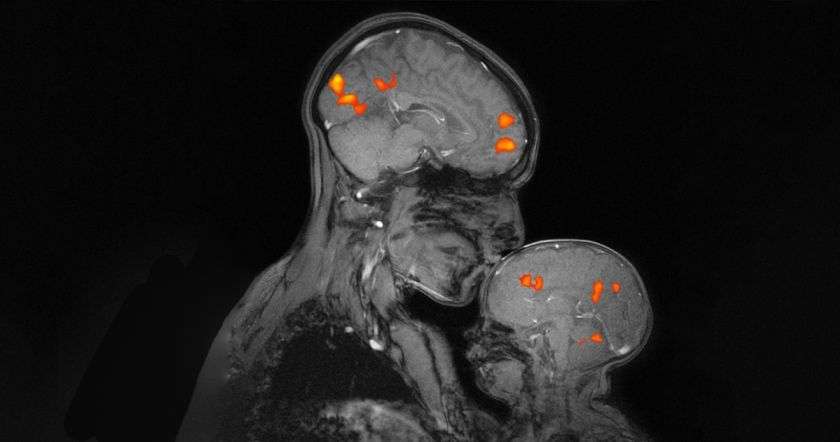

Վերջերս կենսաբանները մի ցնցող հայտնագործություն են արել։ Պարզվել է, որ օրգանիզմում առկա մի հորմոնի՝ օքսիտոցինի (Oxytocin) քանակությունը երեխայի մոտ ավելանում է, երբ նա հպվում է բիոլոգիական մորը։ Որդեգրված երեխաների մոտ այս հորմոնի քանակությունը հաստատուն է մնում։

Վերջերս պարզվել է, որ, բացի մինչ այժմ հայտնի մի շարք կարևոր գործառույթներից, օքսիտոցին հորմոնը պատասխանատու է երեխայի՝ սոցիալական խմբում ինքնաարտահայտման համար։ Օքսիտոցինի բավարար քանակության դեպքում երեխան կարող է ագրեսիվ պաշտպանել ինքն իրեն՝ պատասխանել իրեն ծաղրողներին։ Եվ պատահական չէ, որ ծնող(ներ) չունեցող երեխաները հաճախ հայտնվում են սոցիումի հետնաբակում՝ ամենևին արժանի չլինելով դրան։ Այս դեպքում, ի հավելումն խախտված սոցիալական նորմերի, երեխայի մոտ բացակայում է անհրաժեշտ քանակի օքսիտոցինը, որը շատ բացասական է արտահայտվում նրա սոցիալական վարքագծի վրա։

Ծնողները, հաճախ գրկելով ու սիրելով երեխաներին (բնական պահանջ է, անկախ իրենցից՝ անում են բոլոր ծնողները), օգնում են երեխաների մոտ գեներացնել բավարար քանակությամբ օքսիտոցին, և երեխան կարող է կայուն կանգնել կյանքի ողջ ընթացքում, իսկ լքելով երեխաներին, դարձնում են նրան ֆիզիոլոգիապես ոչ ամբողջական, իսկ հասարակության մեջ՝ ոչ ամբողջական անդամ։ Գուցե այստեղից էլ առաջացել է ժողովրդական իմաստուն խոսքը՝ «Արյունը ջուր չի դառնա»՝ նկատի ունենալով հարազատների կապվածությունը։